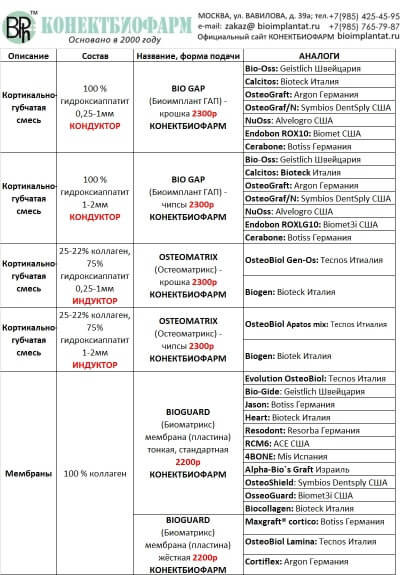

Сравнительная таблица остеопластических материалов